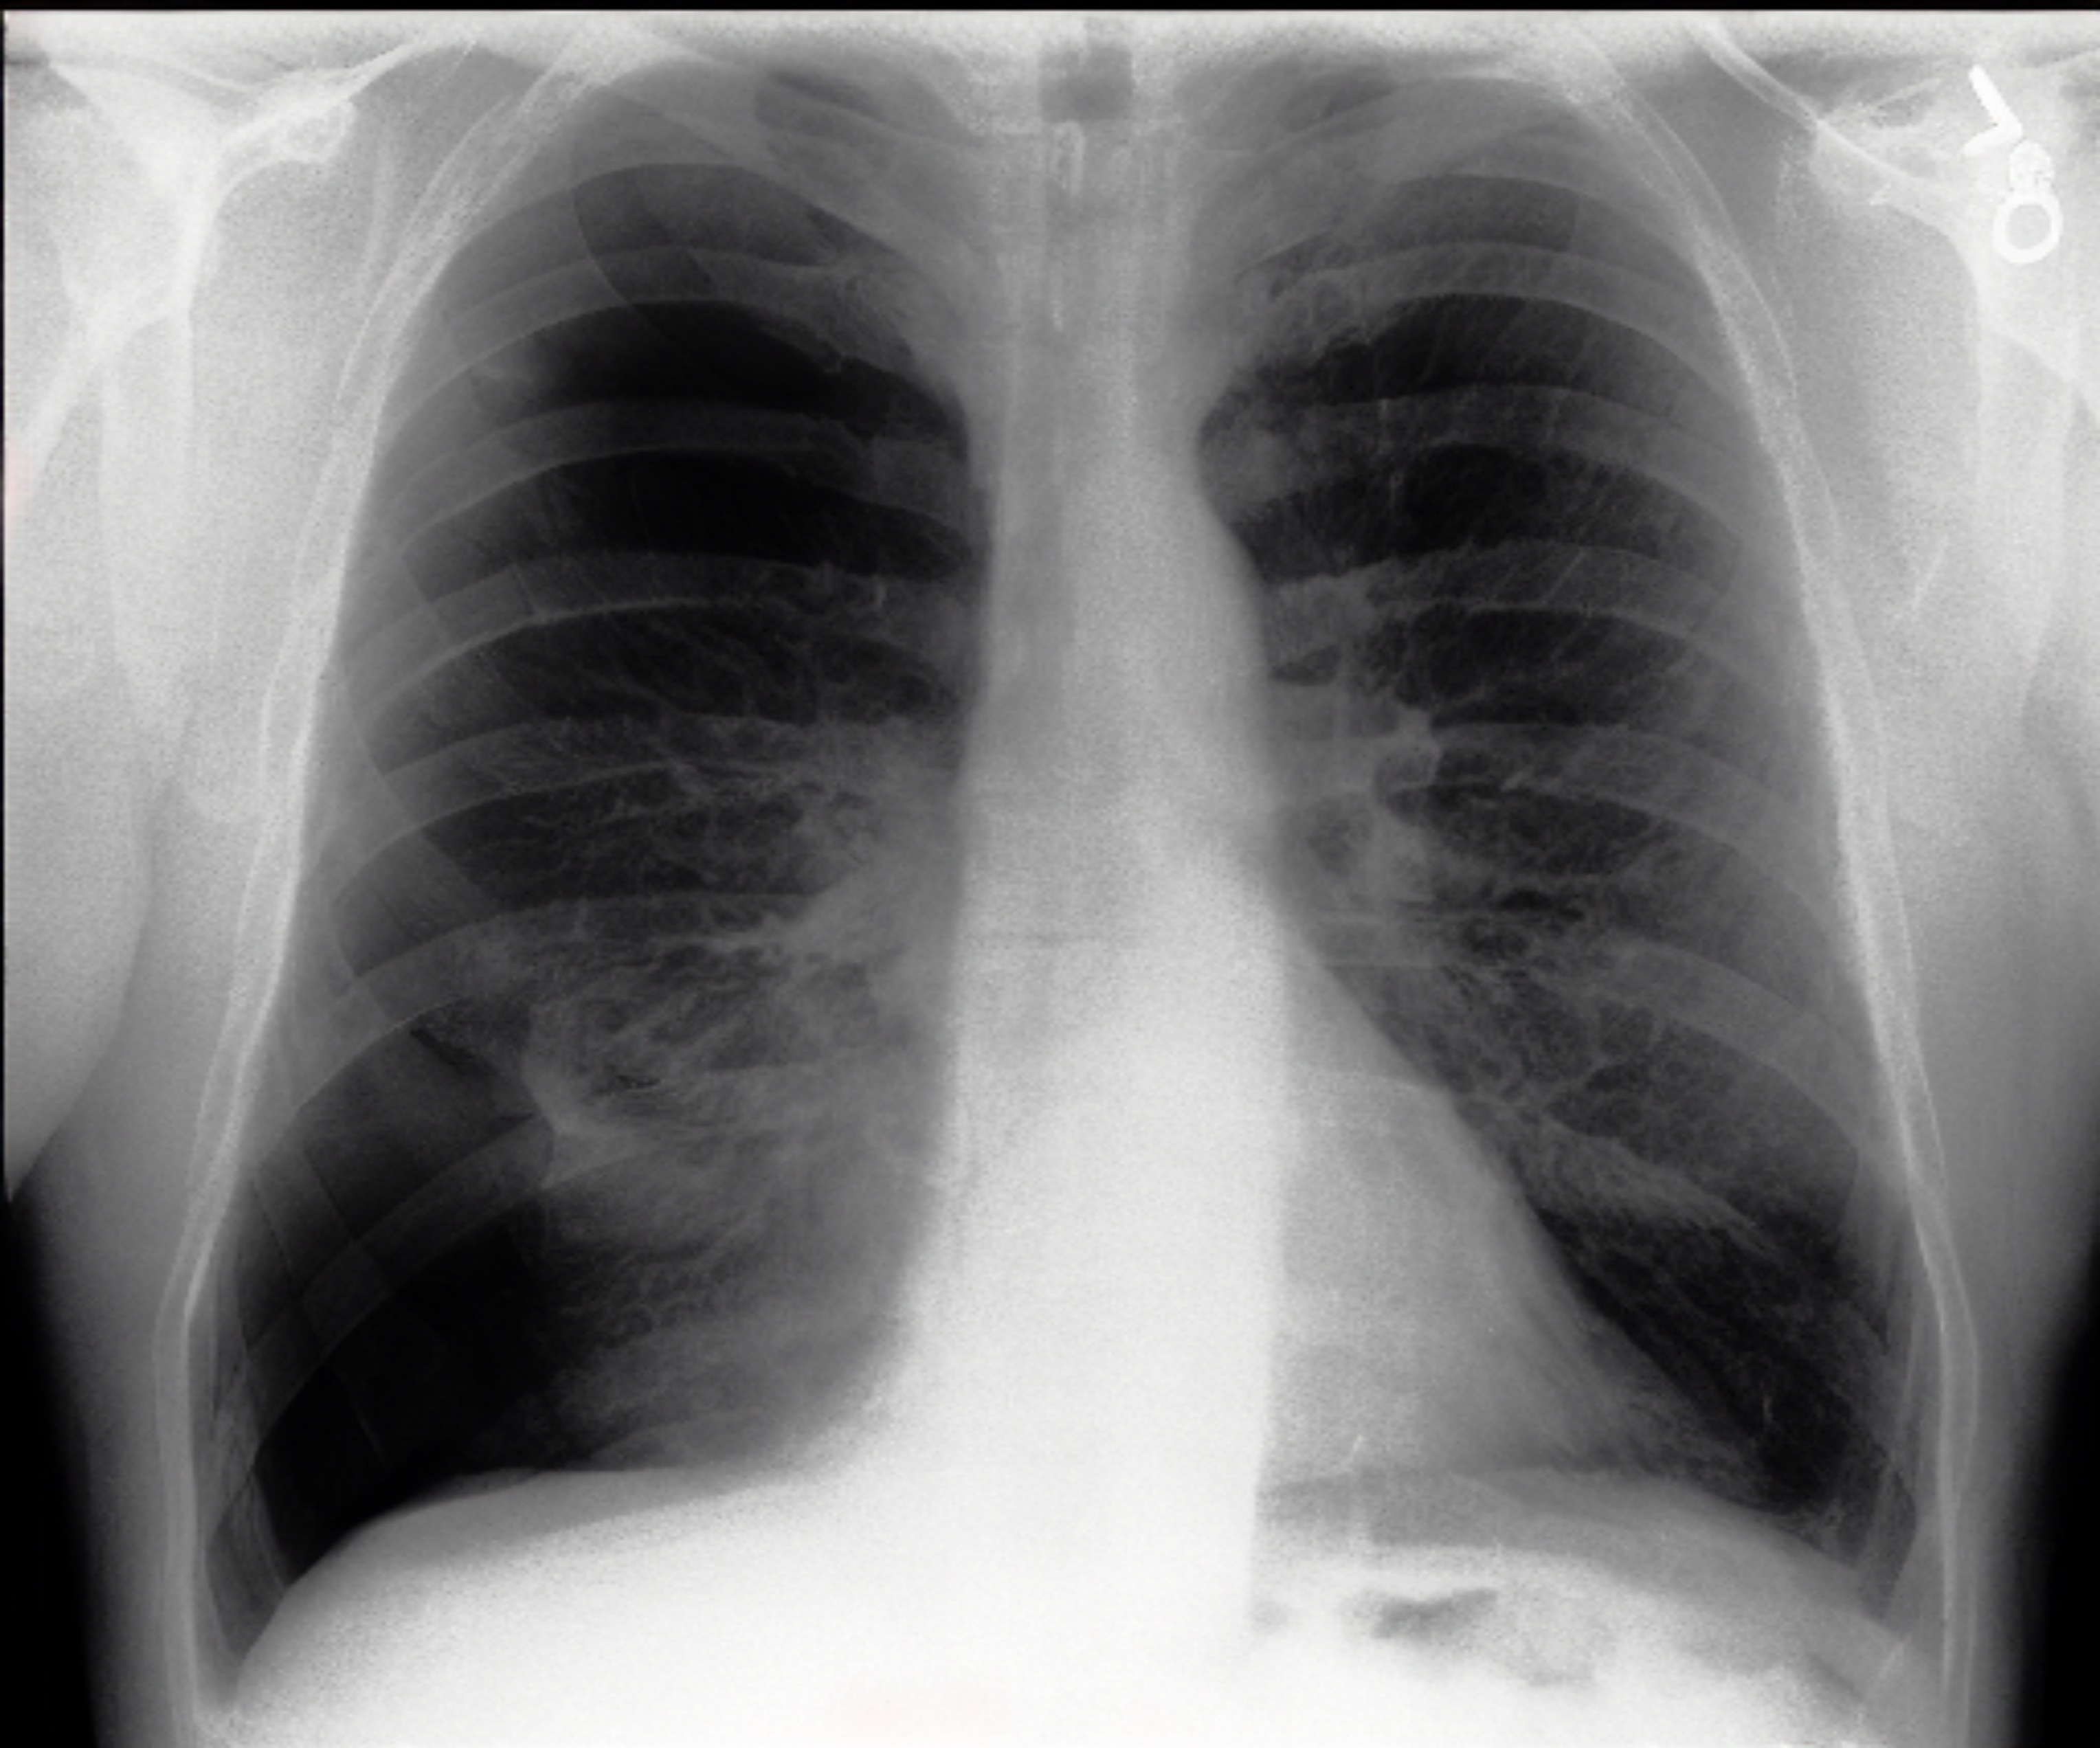

Table 1: Sample chest X-ray (CXR) images. The top row shows a normal CXR, while the remaining rows display CXRs with various pathologies, including right-sided cardiomegaly, large pneumothorax, viral pneumonia, and pulmonary edema.

Normal Chest X-ray Image

[Uncaptioned image]

Right-sided Cardiomegaly Large Pneumothorax

[Uncaptioned image] [Uncaptioned image]

Virus Pneumonia Pulmonary Edema